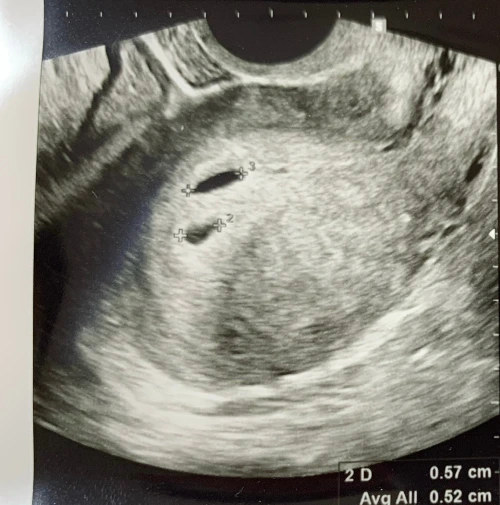

“아기집은 2개가 보이네요.”

아마도 가장 작은 점이었던 것이 자연도태된 것이다. 선생님은 아직 정상적인 아기가 되기 전에 사라진 것이기 때문에 언제든 이런 일이 있을 수 있다고 사전에 이야기는 했었다. 그럼에도 만약 내가 선택적 유산을 선택했더라면 다른 아이가 사라지고, 지금은 사라진 아이가 살아서 아기집이 되고, 건강한 태야가 될 수 있지 않았을까?라는 쓸데없는 가정을 해보면 사라진 아이도 생명이 아니라는 이유로 쉽게 잊어버리긴 어렵다.

이런저런 생각이 이어지지 못한 것은 바로 초음파 검사에서 아기집으로 커진 두 아이의 심장 소리를 들려주었기 때문이다. 흔한 TV 속 장면에서는 이 타이밍에 남편이자 예비 아빠로서 남자들이 눈물을 흘리던데, 눈물이 많은 나조차도 그런 눈물이 나오지는 않았다. 마냥 신기하다는 감정이 먼저 들었고, 정말 이제는 생명이 아내의 아직 불룩하지 않은 배 속에 있다는 게 믿기기 시작했다. 시각적인 신호 외에도 청각적 신호를 엄마 배속 그 깊숙한 곳에서, 손톱보다도 작은 심장에서 우리에게까지 보내고 있는 것이다. 그 소리들을 듣기 시작하면 ‘생명의 태동’이라는 단어가 바로 머리에 떠오른다. 생명이 없던 상태에서 심장이 마구 뛰는 아이들이 탄생하는 신비. 우리는 본격적인 임신과 출산 준비에 이르렀다.